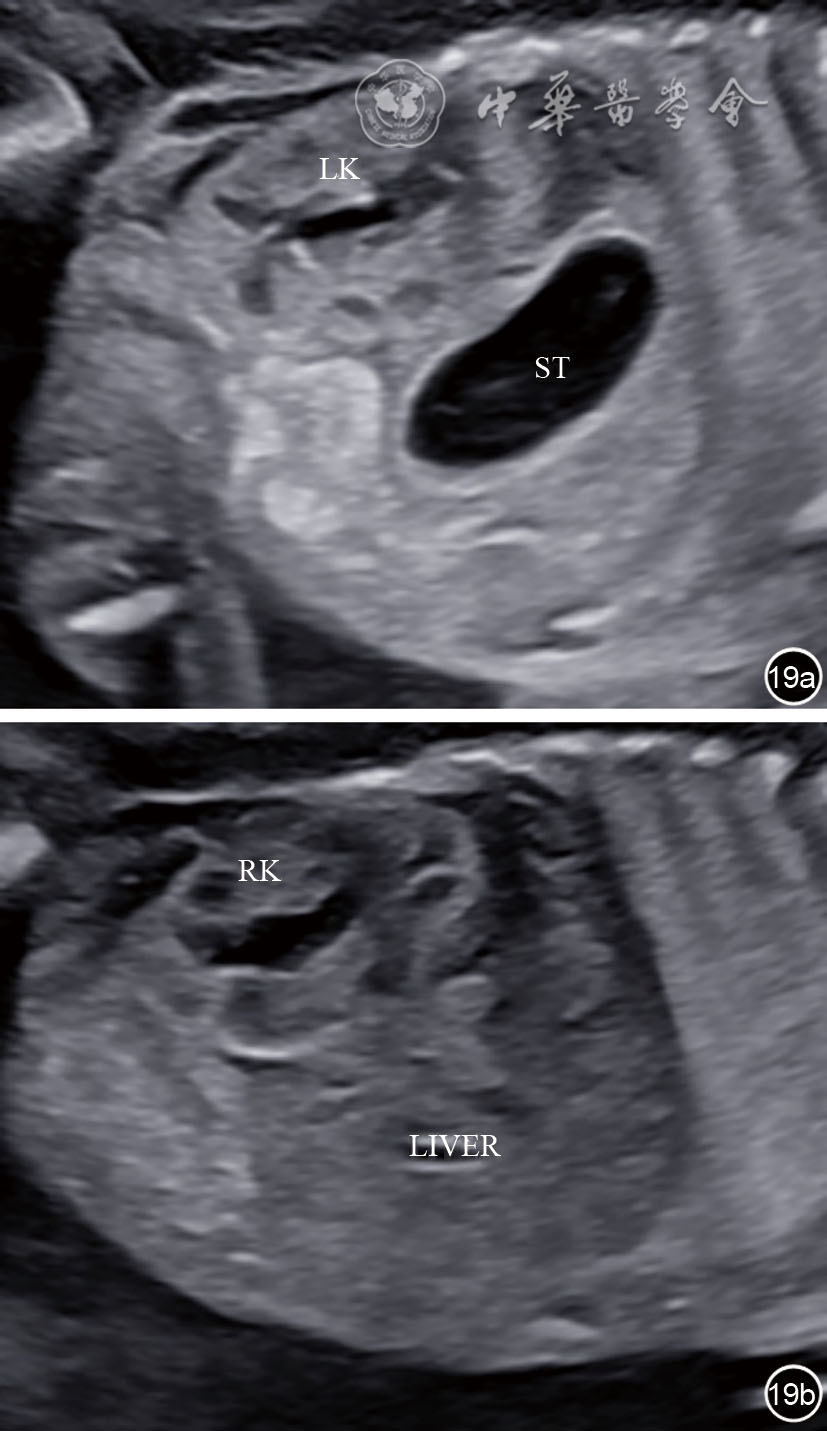

图19 肾脏矢状切面超声图像。图a为左肾矢状切面;图b为右肾矢状切面 注:ST为胃泡;LIVER为肝脏;LK为左肾;RK为右肾